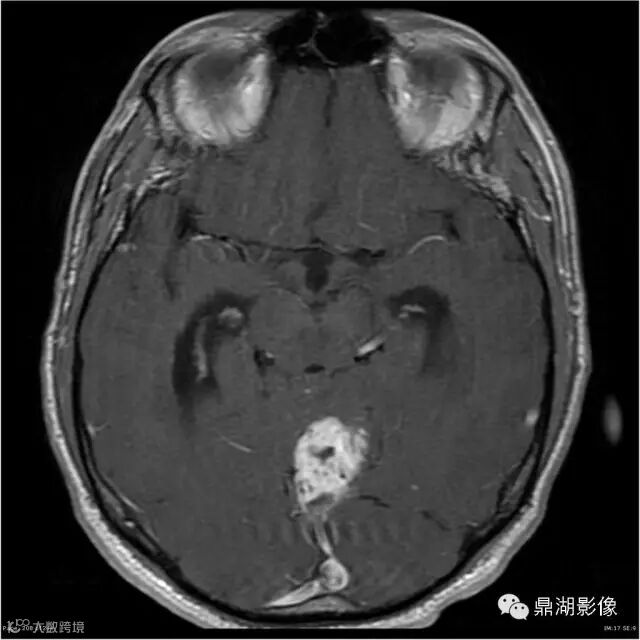

Axial C+

影像:可见一个约43 x 36 x 31mm的从小脑蚓部延伸而来的占位,T1WI、T2WI呈高低混杂信号,病灶周边见流空血管影及水肿带,增强病灶明显强化,中心见无明显坏死区,它紧靠左小脑幕上。第四脑室受压变窄,室管膜水肿,可见脑桥及延脑扁桃体进入枕骨大孔。

本例为一例实质性血管母细胞瘤。实性血管母细胞瘤CT平扫示病灶呈等或高密度,增强后可见明显强化。MRI平扫通常病灶很不均质,T1呈稍低信号为主的较混杂信号,T2呈等、高信号,DWI通常呈低信号或等信号。文献报道,实性血管母细胞瘤较典型的表现为瘤内及瘤周扩张的流空血管影,瘤周中、重度水肿。因此,小脑半球区的单发肿块伴流空血管影,周围大片水肿以及增强后肿块明显强化"形态规则"边界清楚,此时应将实性血管母细胞瘤考虑在内。